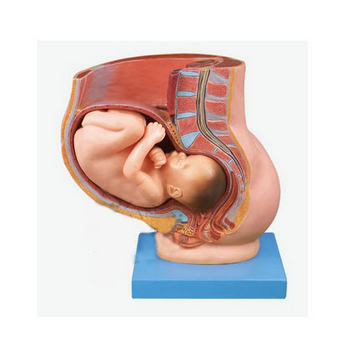

GD/A42006骨盆含妊娠九個月胎兒模型產品介紹:1、該模型由骨盆子宮和妊娠九個月胎兒兩個部件組成,并顯示子宮、陰道、膀胱、直腸和胎兒、羊膜、胎盤、臍帶等結構,共有38個部位指示標志。2、尺寸:自然...